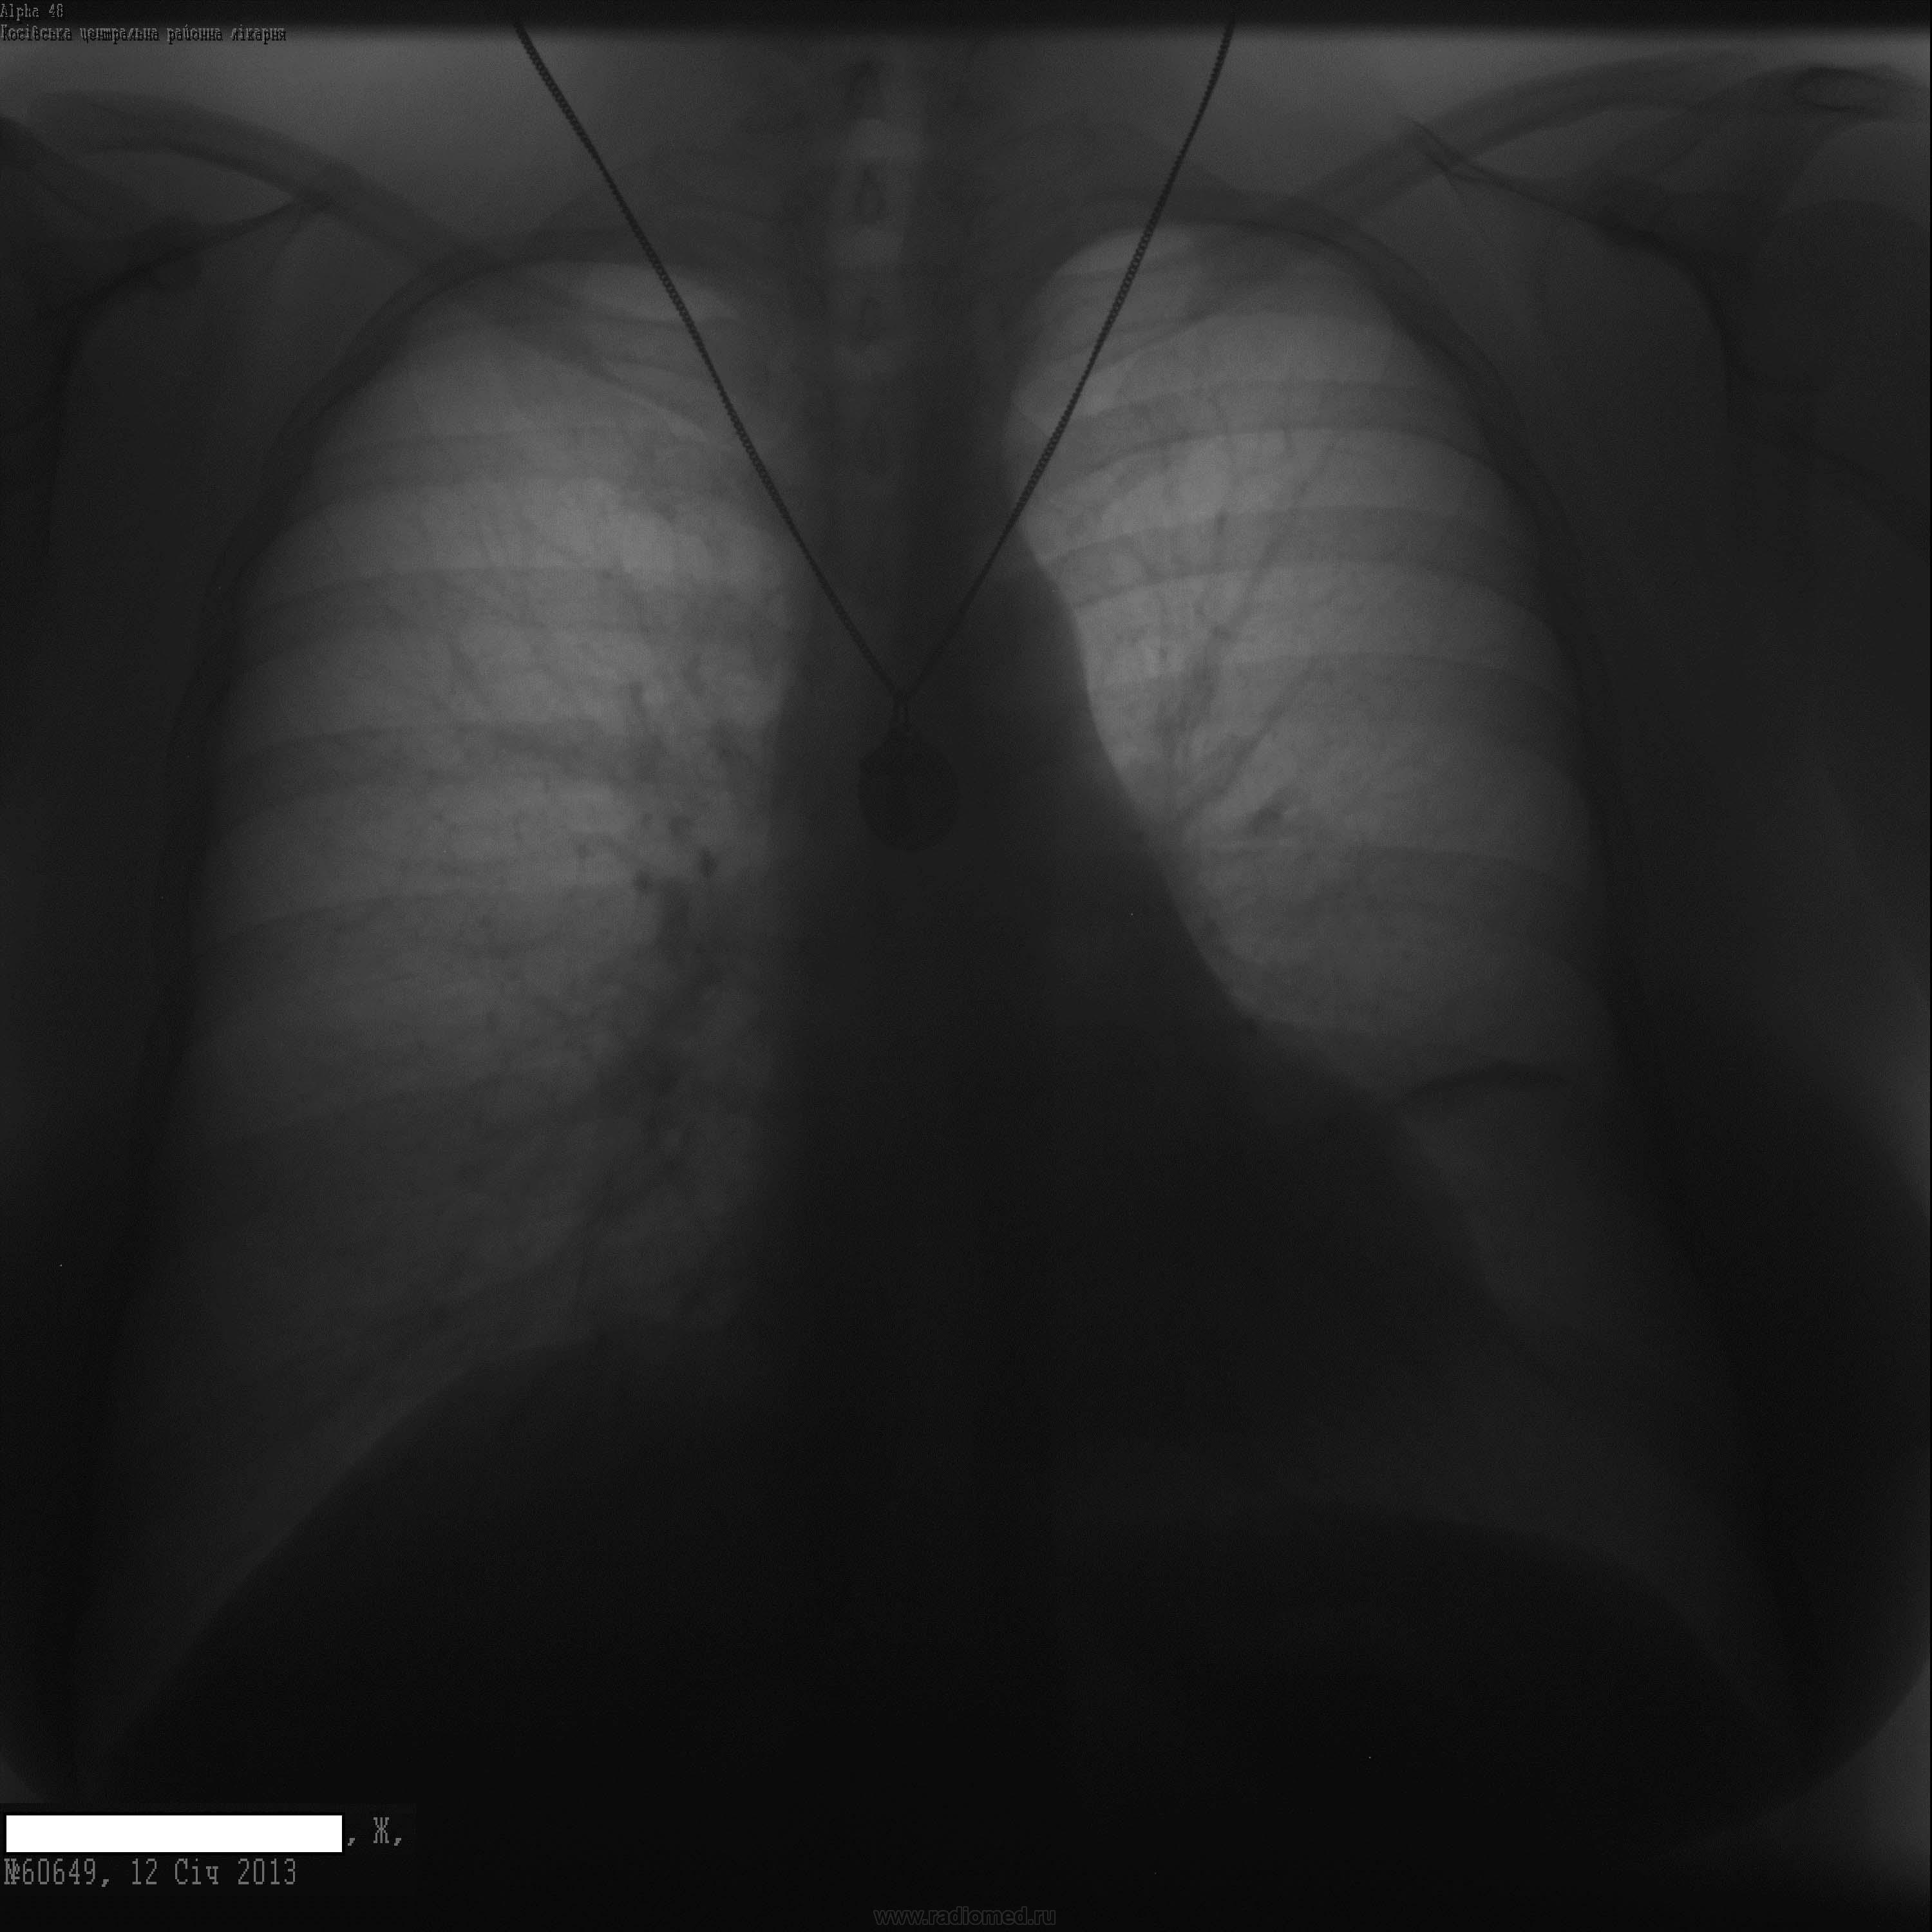

Заболела докторша, 36 лет. Температура 37,1, сильный кашель с отделением мокроты, ослабление дыхания слева, в крови лейкоцитоз 13, СОЭ 15. Нафотографировалась в динамике на фоне антибиотикотерапии. Хочет узнать мнение мирового рентгенологического сообщества.

А я думаю, нет ничего , кроме линейной плевральной спайки слева. Можетбыть, заболела раньше, чем снималась и это- исход.

Исследования 30.12.12, 4.01.13, 7.01.13, 12.01.13.  Вопрос один: а кто устанавливал сроки контролей "докторше" и чем при этом руководствовался?

Сроки контроля, действительно, подобраны наверняка самой пациенткой-"докторша" она или нет-но вот положительная динамика есть. Создается впечатление, что на первом снимке была левосторонняя верхнедолевая (язычковая) пневмония.

Данных за гиповентиляцию нет. "Сухой" междолевой плеврит слева с имеющейся динамикой регресса. Данные за пневмонию также сомнительны. Справа - старые спайки. Неплохо бы врача научить снимать побрякушки с шеи на ФОГК и соблюдать сроки контроля. Если себя не жалеет, то пациенты у неё, наверно, все новогодними ёлками будут - светиться.